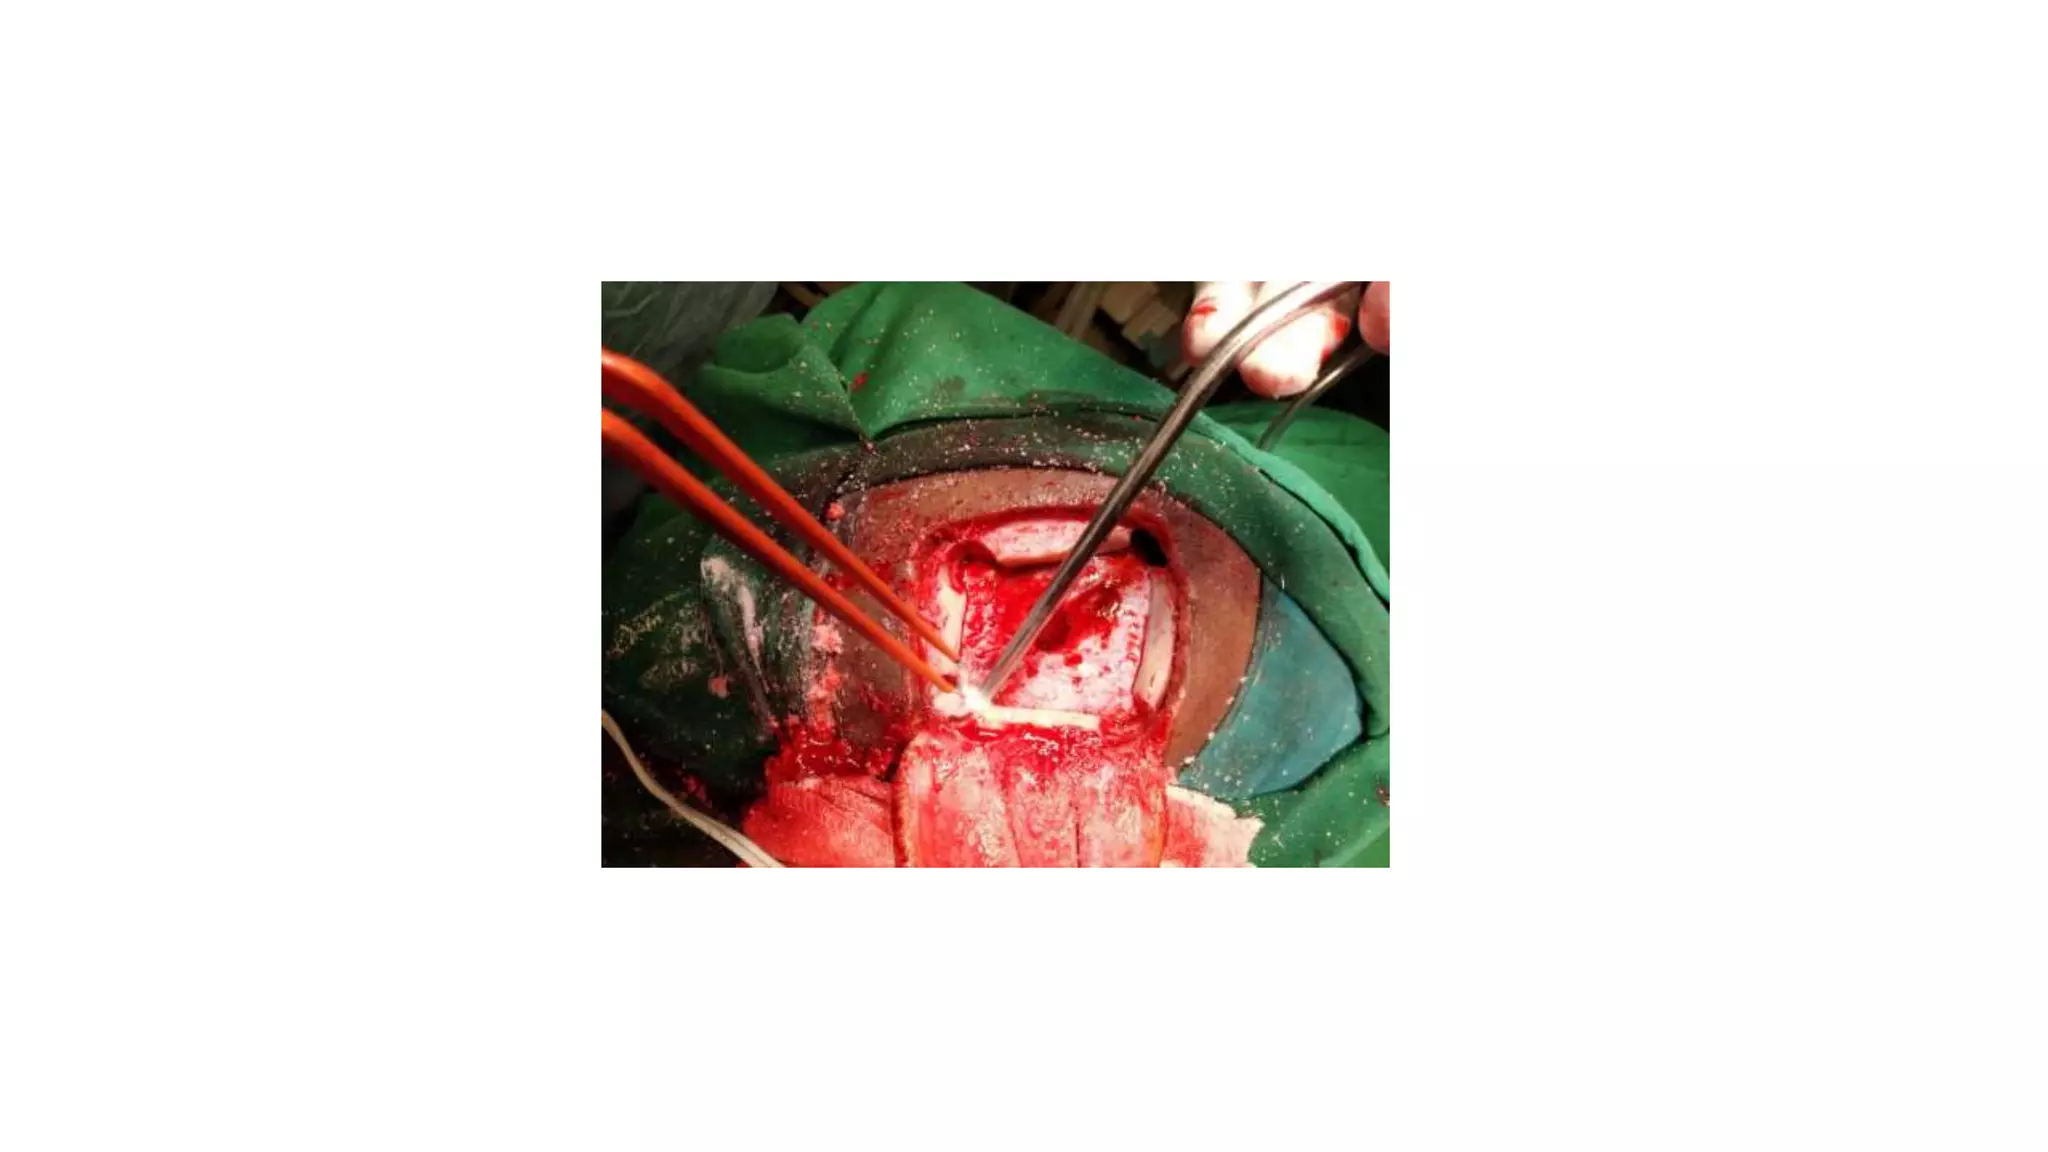

Trans cortical:

Trans callosal:

• No hydrocephalus and dilated ventricles.

• Entry point will be 1.5 lateral to midline to

avoid the superior saggital sinus

• Brain retracted superior callosal arteries

are retracted

• Entry will be between the Fornices and

then into any of the foramen of Monroe

• Enblock cyst excision is possible in trans

callosal approach.